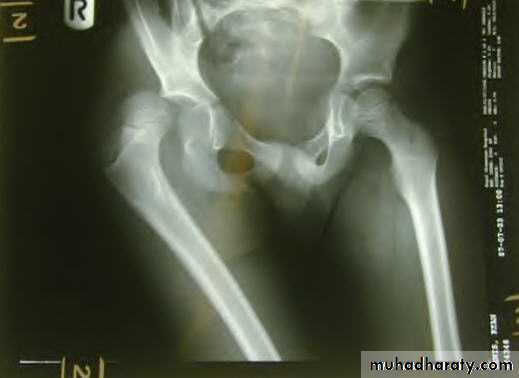

Pathological anatomy and classificationThe most useful is that of garden which is based on amount of displacement apparent in the pre-reduction x-ray of the neck femur.

Stage 1

impactedStage 2

complete fracture UndisplacedStage 3

complete with moderate displacement.Stage 4

severely displaced fracture.Fracture neck femur has poor capacity for healing

Is it displaced ?:Radiological classification

GRADE 1

:the femoral head is in its normal position or tilted into valgus and impacted on the femoral stump.GRADE 2

The femoral head is normally placed and the fracture line may be difficult to diagnosed

GRADE 3

The femoral head tilted out of position and the trabecular marking are not in line with those of innominate bone.GRADE 4

The femoral head trabeculae are normally aligned with those of innominate bone.